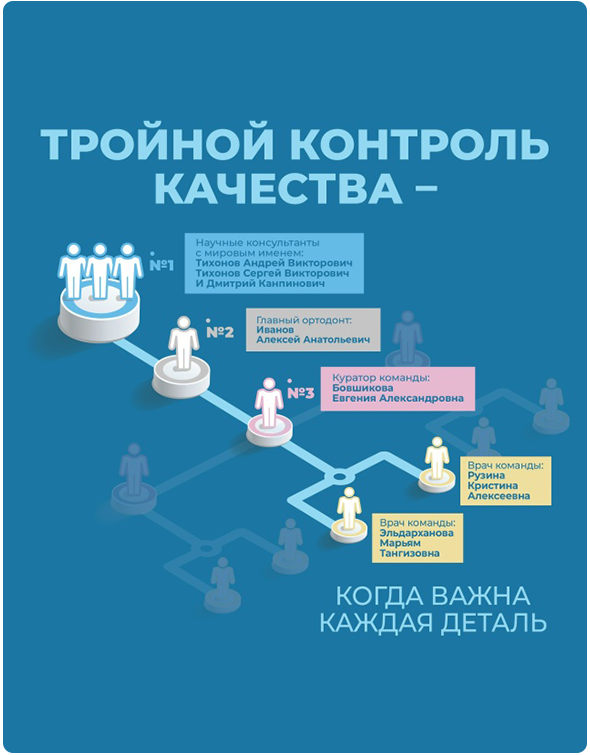

Специалисты клиник «Полный порядок» подбирают методику коррекции индивидуально, с учетом возраста, клинической ситуации и финансовых возможностей пациента. Так, в детском и подростковом возрасте для раннего лечения эффективны съемные аппараты - пластинки и трейнеры, а также тренажеры для губ и языка, занятия с логопедом, лечение частичной брекет-системой. Для взрослых пациентов мы рекомендуем самостоятельно лечение брекет-системами или капами элайнерами или в сочетании с хирургией. В некоторых случаях врач может комбинировать различные методики.